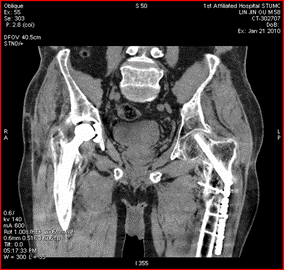

高能量X射线可以去除高密度金属引起的伪影

常规CT 宝石能谱CT

140keV能量成像可以除去金属引起的伪影,更加清晰观察术后情况